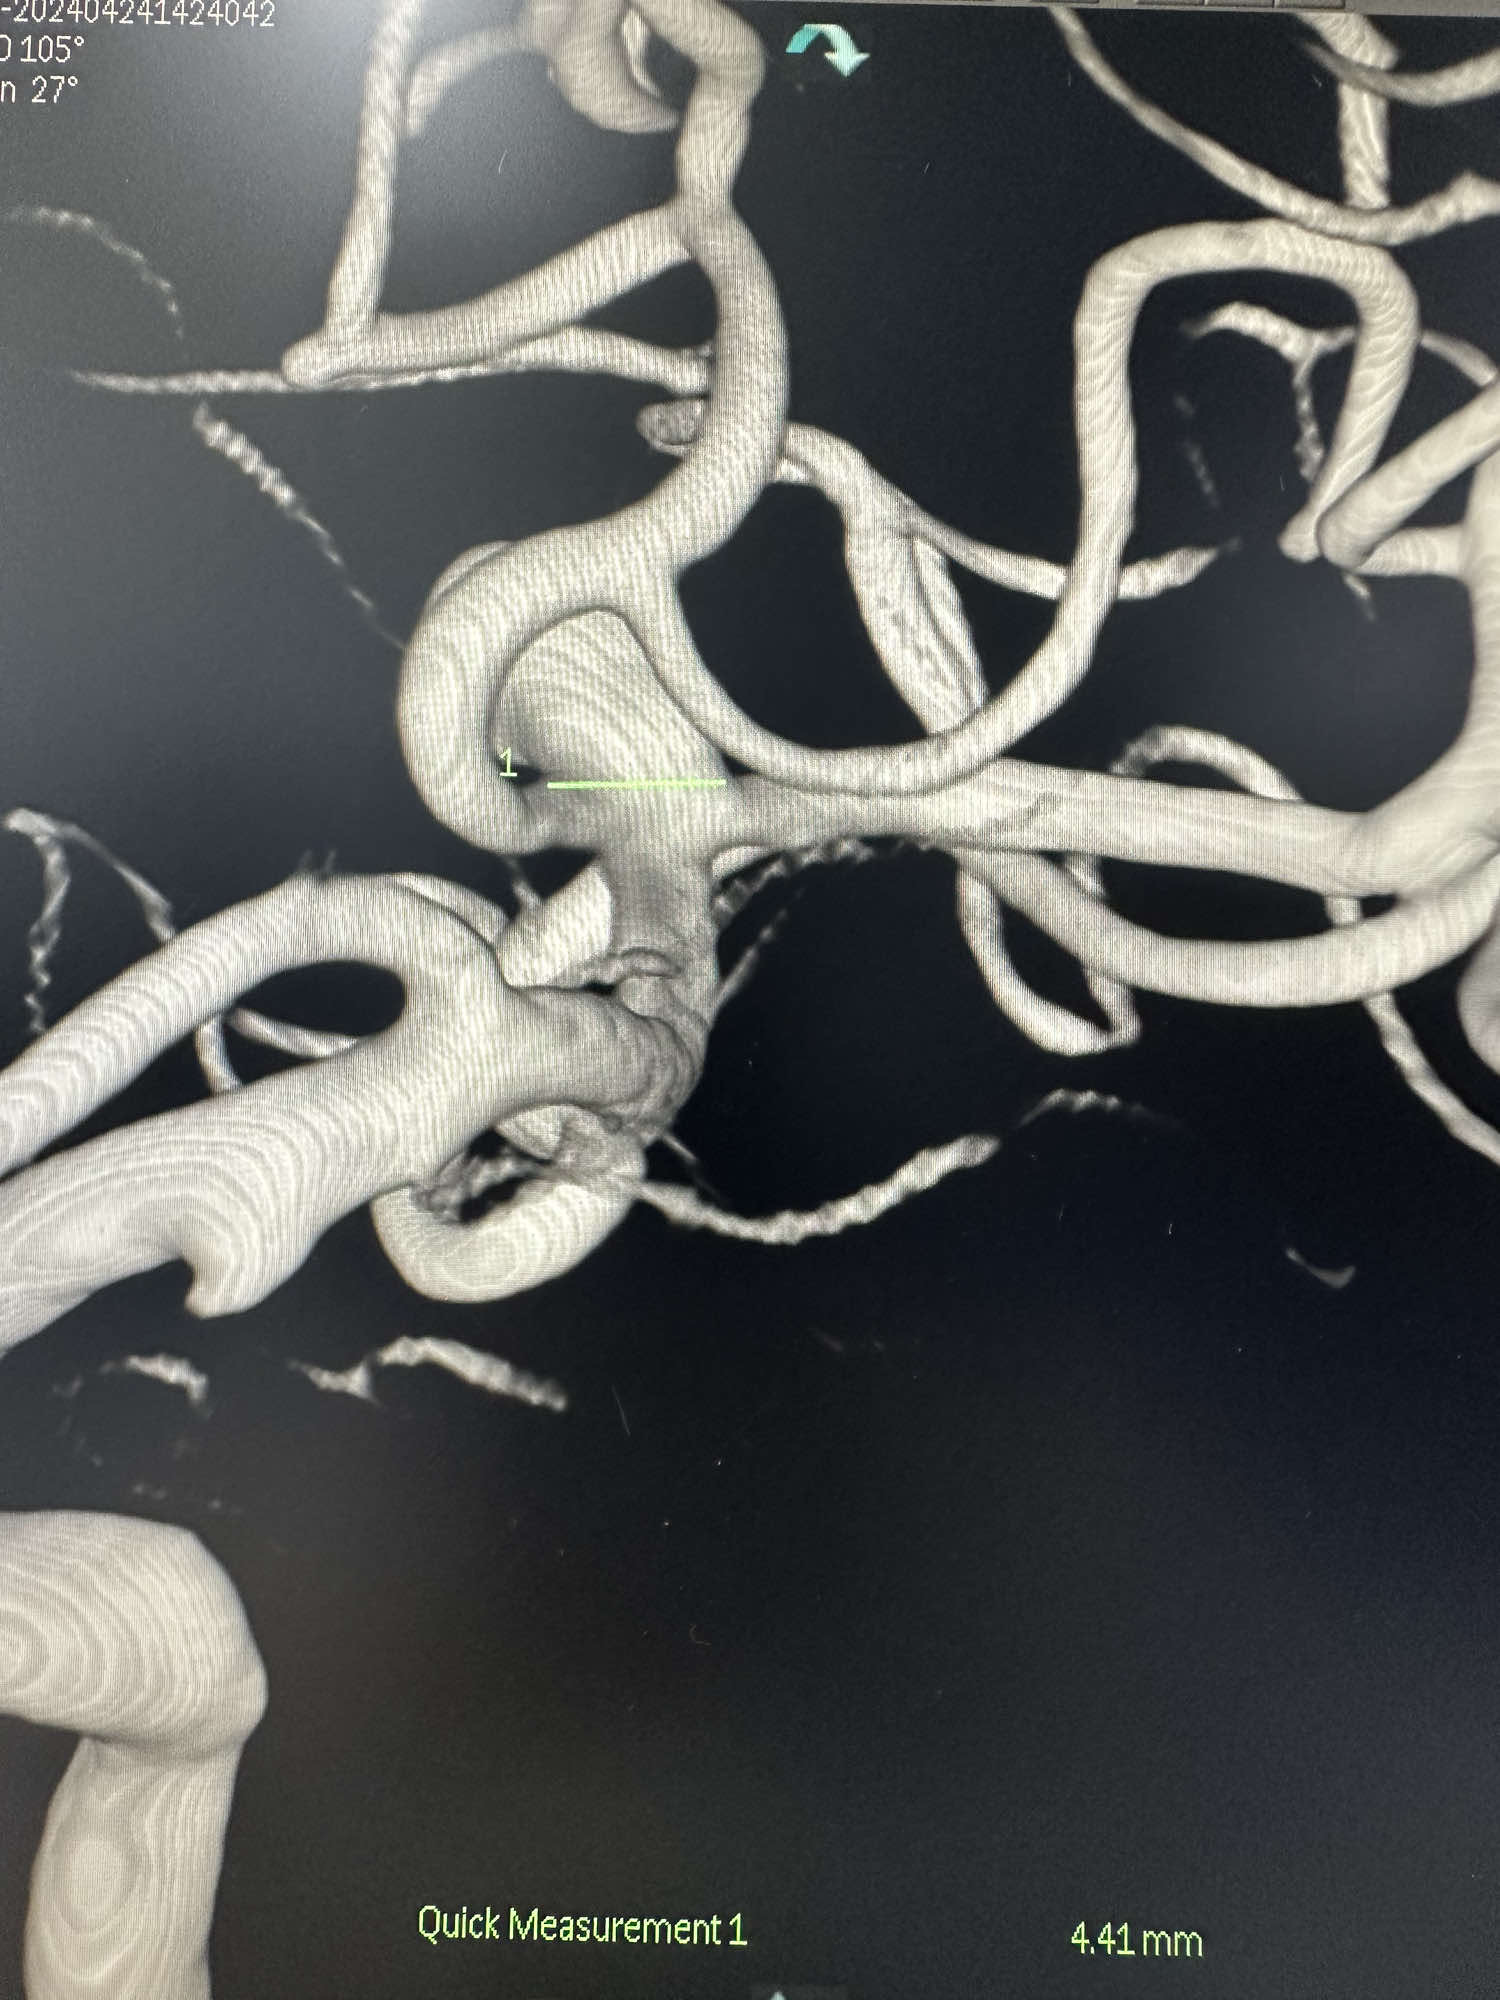

分叉处动脉瘤的瘤颈部月4.4mm

大脑中分叉处的动脉瘤